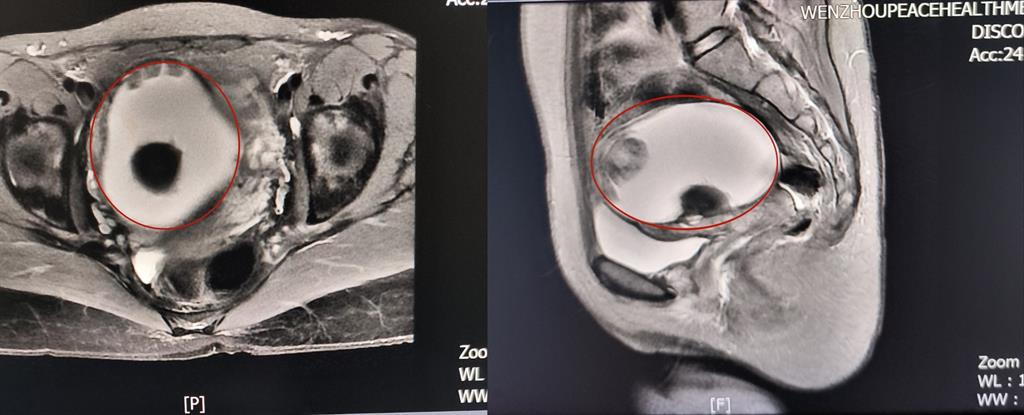

卵巢腫瘤?為進(jìn)一步明確診斷,A女士在方主任建議下做了增強(qiáng)磁共振,影像結(jié)果提示:盆腔右側(cè)團(tuán)塊狀占位伴多發(fā)成熟脂肪成分大小約89*100*71mm,考慮畸胎瘤可能性大。謎團(tuán)逐漸解開,原來那個“怪胎”可能是畸胎瘤在作祟。